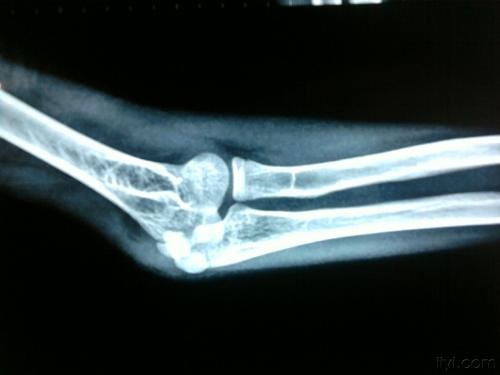

肘关节脱位图

肘关节脱位是临床上骨折后的一种常见状况,发病时有韧带、骨关节及肌肉组织损伤等伴随着出现。

如果不及时治疗的话,就会逐渐过渡向肘关节僵硬转变。肘关节僵硬使患者的肘关节无法正常活动。还伴随着疼痛的产生,给患者的日常生活带来了很大的不便。